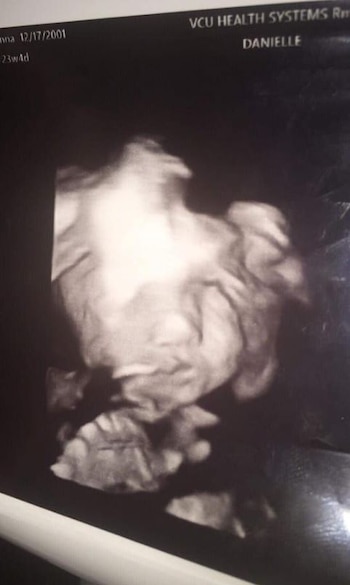

Una madre de Virginia, en Estados Unidos, conoció la "cara de demonio" de su hija gracias a un ultrasonido. Las "aterradoras" imágenes sorprendieron a la joven de 17 años y causaron revuelo por el rostro que la bebé dejó ver antes de su nacimiento, durante una sesión con el especialista médico.

"Parecía normal, luego descubrimos que era una niña, se lo pusieron de nuevo en la cara y luego ella … abrió los ojos y sonrió", escribió Alston en su red social.

La joven de 17 años publicó dos imágenes de su bebé que apareció sonriendo de forma extraña y que causó en sus padres una reacción de miedo.

"Estos ultrasonidos fueron tomados el mismo día. Nunca había visto nada igual, pero amo mucho al bebé diablo", aseguró en tono de burla Iyanna.

La originaria de Richmond, Virginia, declaró a Kennedy News and Media que quería conocer el sexo de su bebé de 24 semanas, pero mientras el doppler giraba por su vientre conoció las imágenes diabólicas de su hija que pronto nacerá.

Iyanna Alston se asustó cuando su bebé la vio con los ojos muy abiertos y mostró una rara sonrisa.

"Dije: 'se ve como un fantasma' y el médico dijo: 'sí, eso es muy [normal]'. Ella se veía un poco loca", agregó Iyanna.

"La mayoría de los bebés se esconden de la cámara. Me miró directamente y me asustó un poco porque la habitación estaba oscura", explicó.

"Algunas personas de Internet pensaron que ella era falsa, pero ese es mi bebé en la vida real allí. El papá también estaba allí. Le sorprendió la noticia de que ella era una niña, porque tiene dos hijos y pensó que iba a ser otro niño. Solo nos reíamos del escaneo", explicó la joven que acostumbra publicar contenido de bebés en su Facebook.

"Puedes ver su naricita en (la otra imagen). Se nota que es realmente hermosa", finalizó Iyanna Alston.

La joven madre publicó un comentario más reciente donde demostró el gran amor que ya profesa por su hija que aún no nace: "Te amo y siento que vamos a través de algunos duros caminos, pero te prometo que no te voy a dejar caer nunca princesa ❤️❤️".